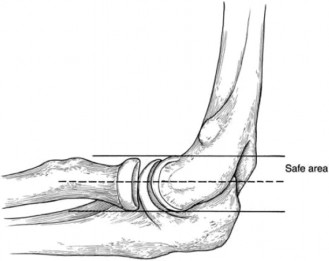

Physicians should obtain a complete set of x-rays. Special views include the modified Westpoint axillary (Fig. 2–43B) to evaluate for glenoid loss and the stryker notch view (Fig. 2–43A) to evaluate the Hill–Sachs lesion. This view brings the posterolateral defect into direct visualization. 3D CT imaging is also very useful for evaluating glenoid bone loss and estimating the size of the Hill–Sachs lesion.